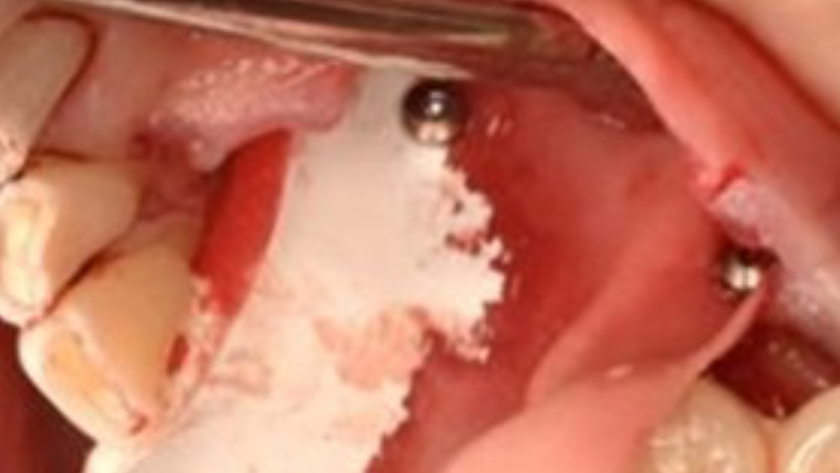

Tooth 22* required extraction in a 49-year-old female patient. The site demonstrated a Siebert Class III defect with a significant vertical discrepancy. The goal was to restore the site with an implant.